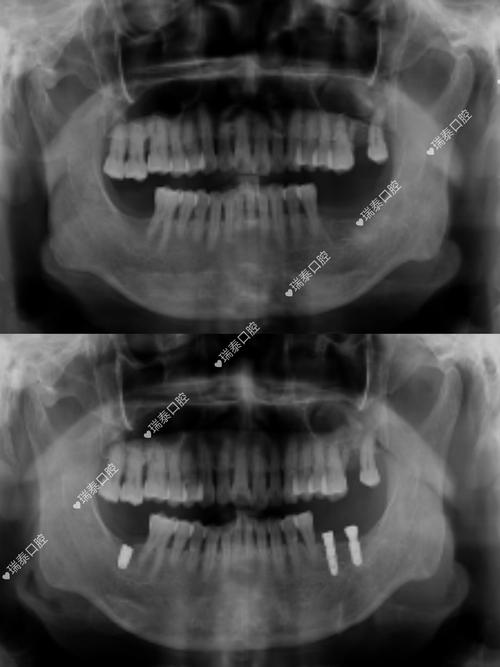

- 其他影像学检查: 对于常规的种植体随访,有时会使用根尖片或全景片,这些检查伪影较小,但显示细节(尤其是三维结构)的能力远不如CT,它们通常用于观察种植体整体位置和骨高度的大致情况,而非精细评估骨结合或微小病变。